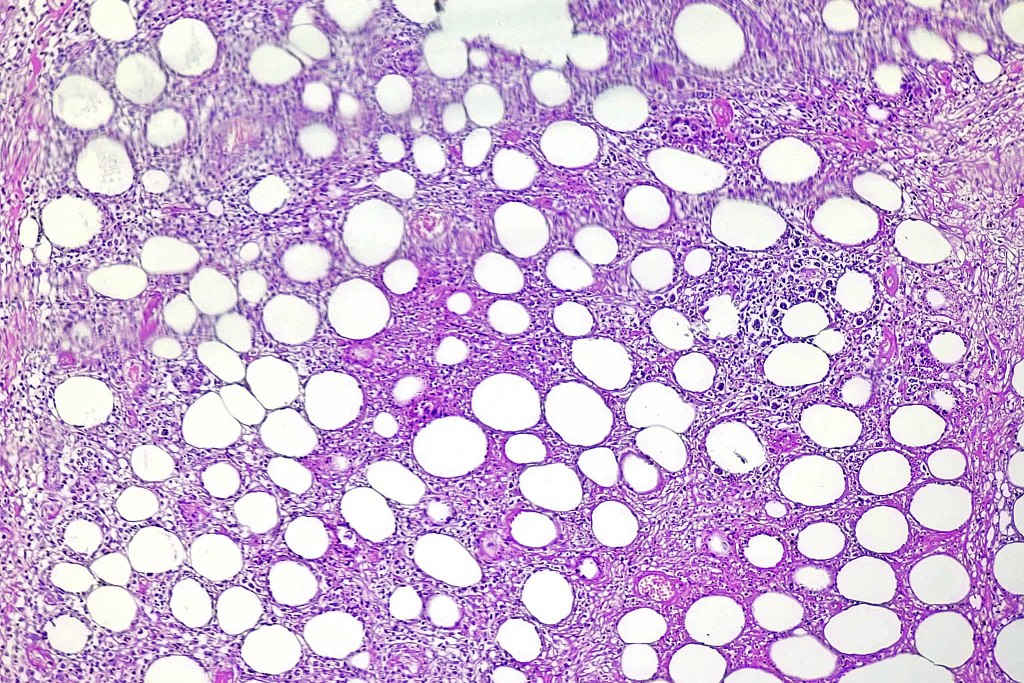

Histological features

•Dense infiltrate involving the lobules of the subcutaneous fat

•Epidermis & dermis are uninvolved

•Atypical lymphocytes with hyperchromatic nuclei & minimal cytoplasm

•Rimming of adipocytes

•Mitoses often abundant

•Fat necrosis with xanthoma cells & nuclear dust

•Variable hemophagocytosis (characteristic bean bag cells)